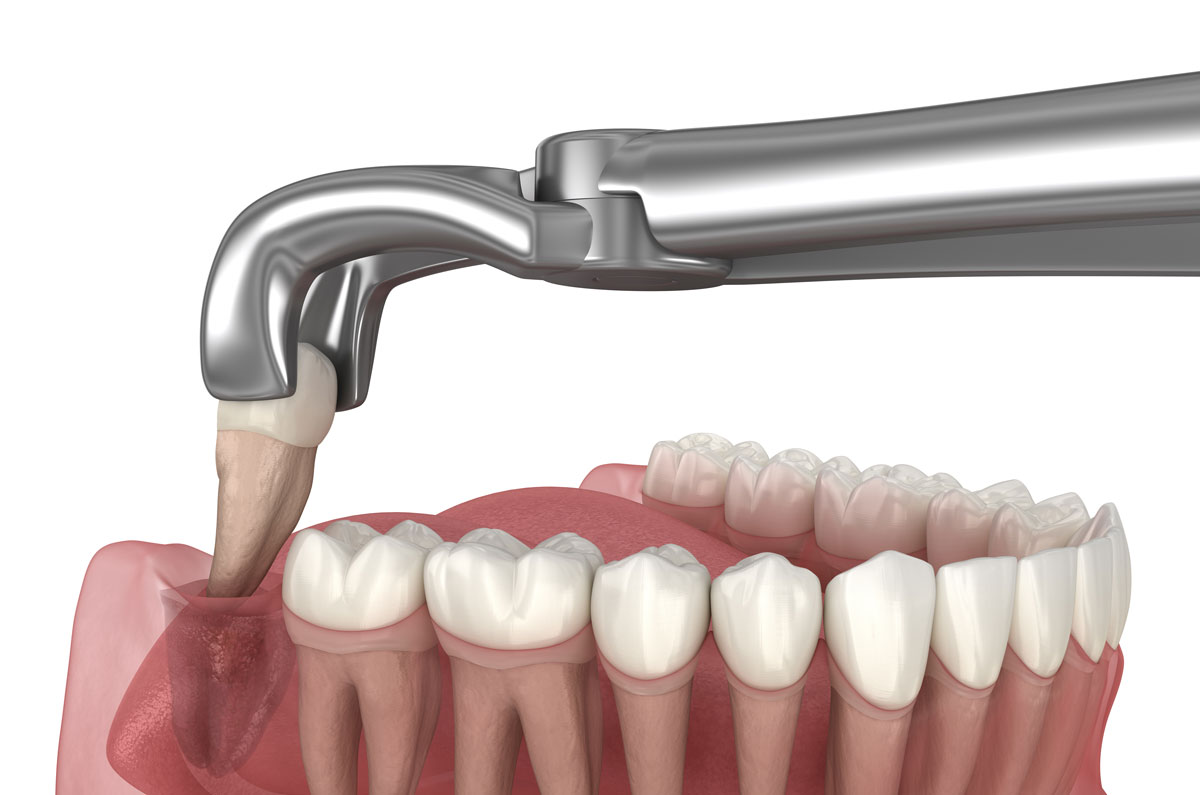

Wisdom Tooth Removal

Safe and professional extraction of impacted or problematic wisdom teeth with minimal discomfort.